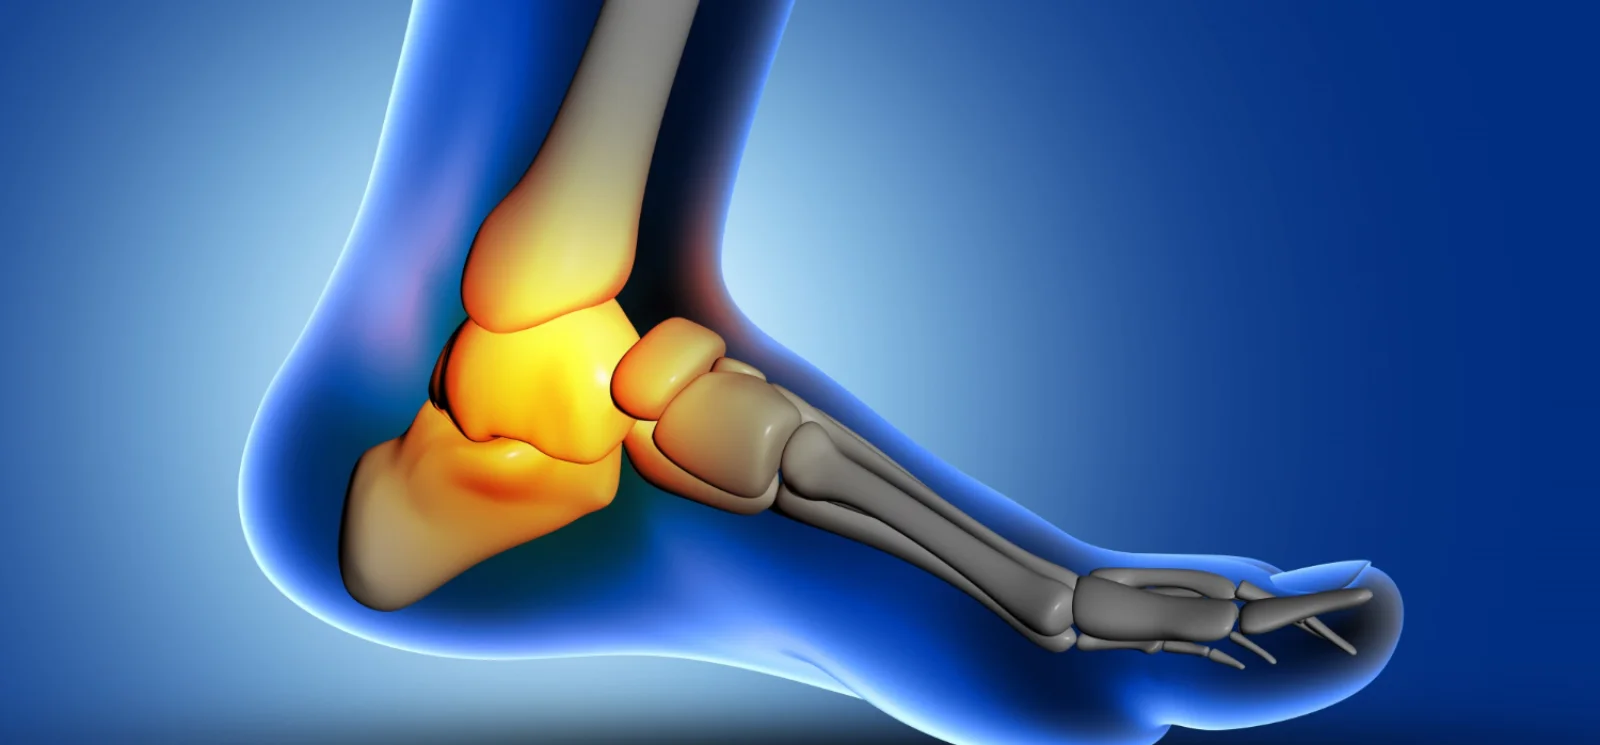

Ankle arthroscopy is a minimally invasive procedure used to diagnose and treat problems inside the ankle joint.

Ankle arthroscopy is a minimally invasive surgical procedure in which a small camera called an arthroscope is inserted into the ankle joint through tiny incisions. The camera allows the surgeon to visualize the joint and treat various conditions such as ligament injuries, cartilage damage, and chronic ankle instability.